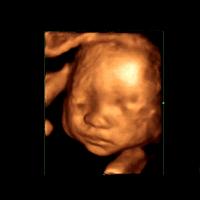

三维超声是在二维的基础上,增加表面成像功能,呈现的是立体图像。

四维彩超能看到宝宝在肚子里的动作和表情,想把彩超的图像作为宝宝人生的第一张照片来收藏,首选四维彩超~

麻麻,我有点累了,换个姿势~

在妈妈肚子里最舒服了,我睡的很香哦!